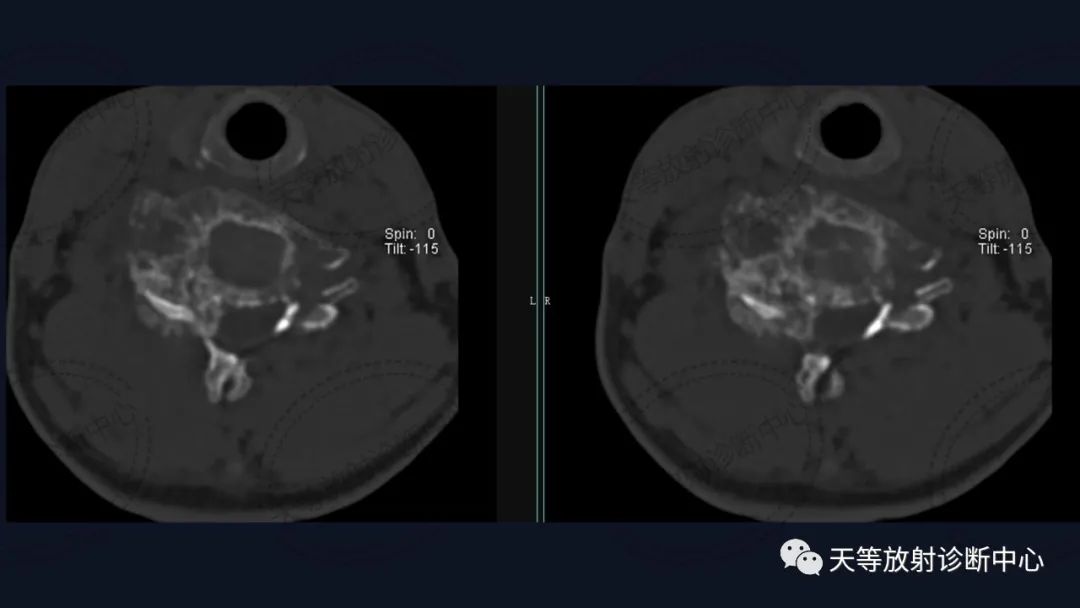

椎体骨质破坏并见大量软骨基质形成

软组织窗骨质破坏呈溶骨性、外生性生长,内部见大量钙化影。

病例1:上图:软骨肉瘤。CT显示椎管及其附件骨质溶骨性破坏,椎体周围软组织肿块并含大量钙化影,钙化呈斑片状、斑点状不定型。整个肿块外生性生长为主,局部突入椎管内。